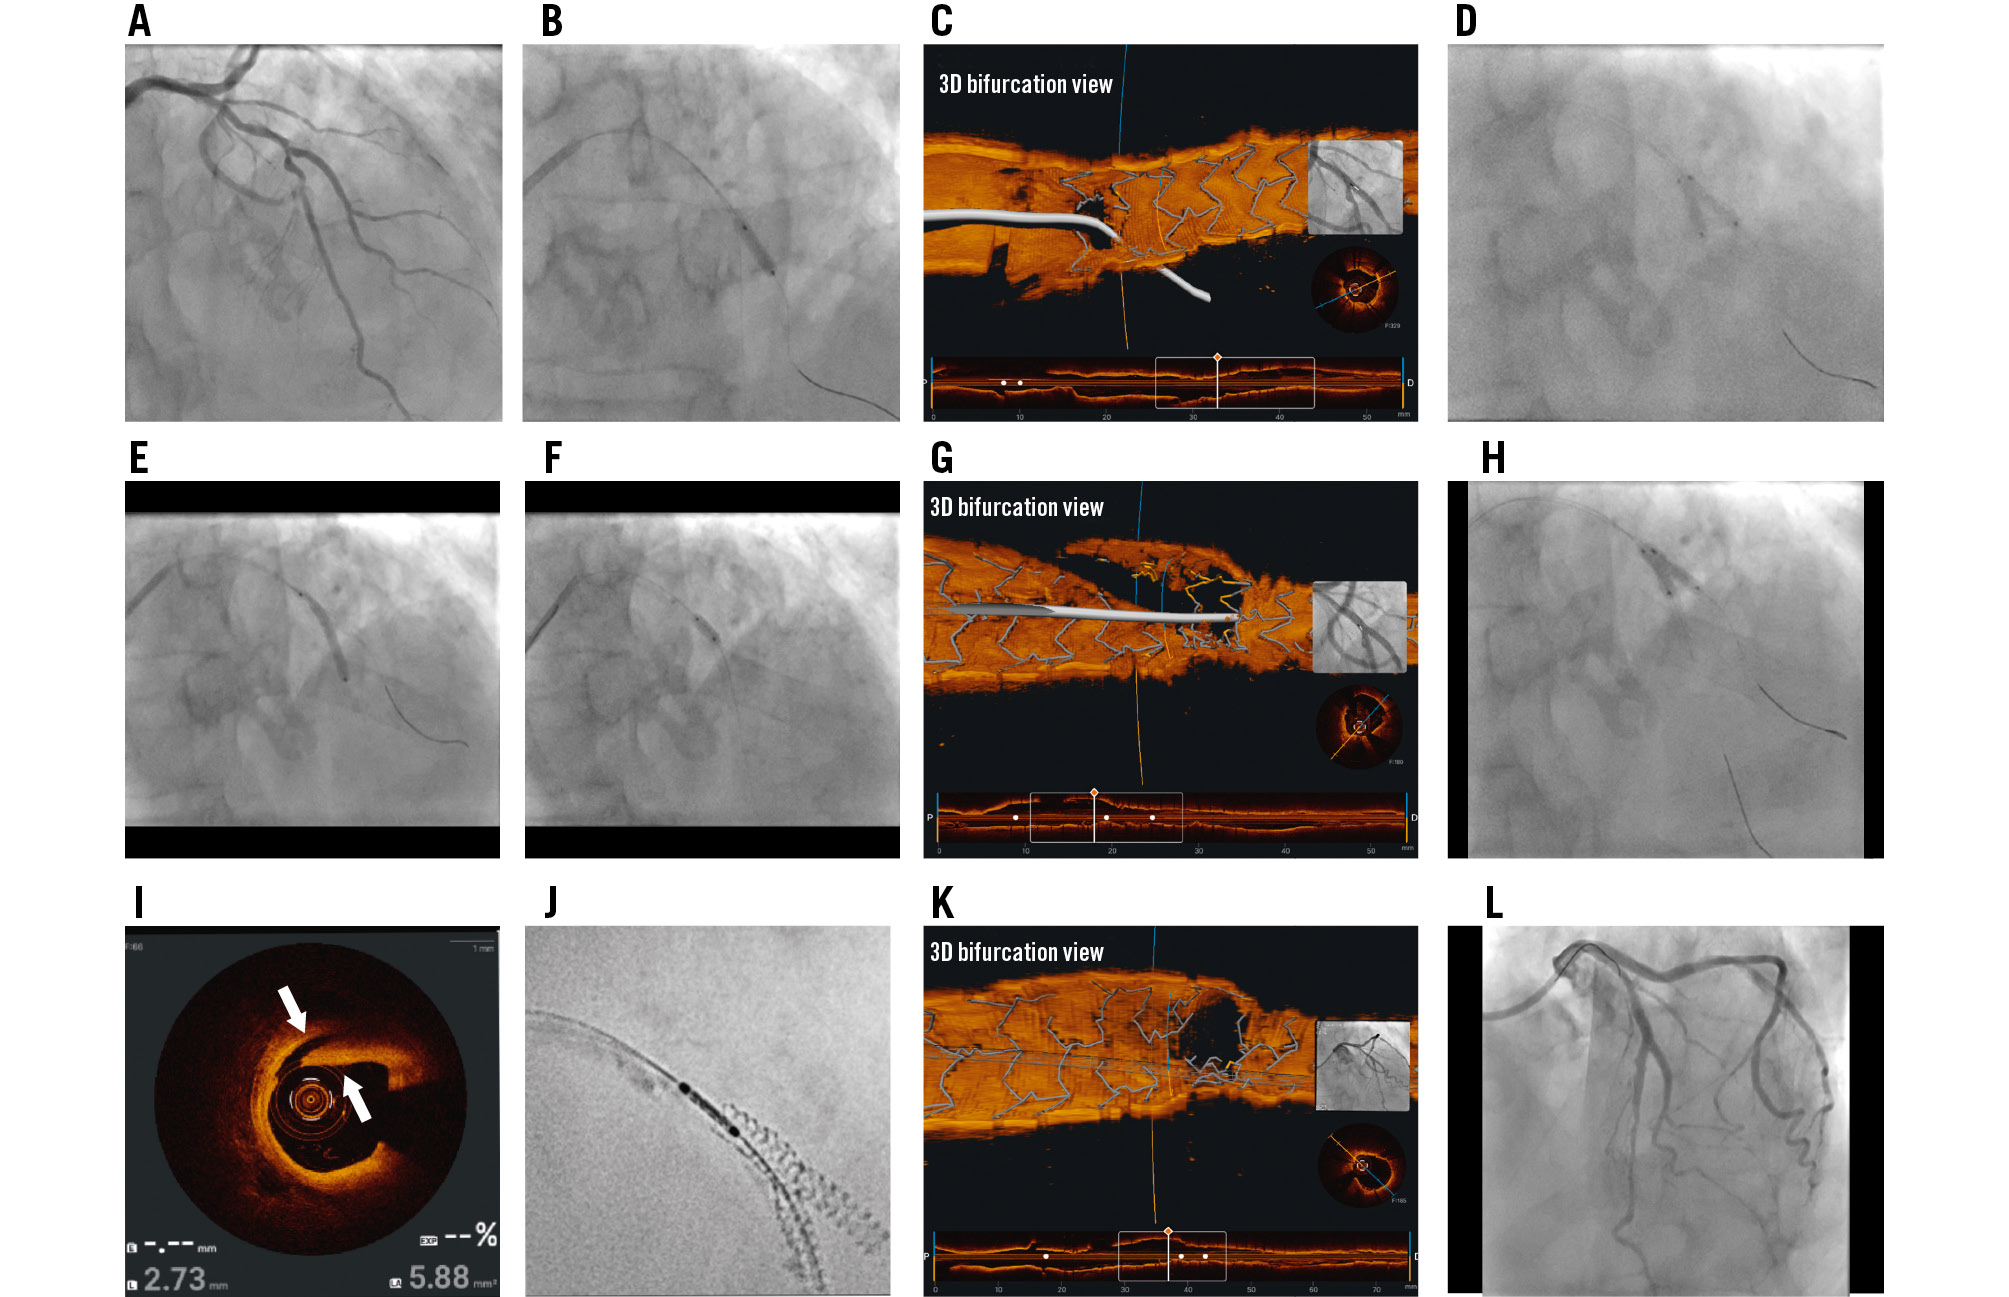

An 82-year-old male presented with exertional angina. Coronary angiography showed a severe mid-left anterior descending artery (LAD) and second diagonal (D2) bifurcation lesion (Medina 1,1,1) (Figure 1A). Baseline optical coherence tomography (OCT) pullbacks were performed in the LAD and D2 arteries, followed by predilatation with a 2.75 mm non-compliant (NC) balloon in both branches and a 3.0×10 mm cutting balloon in the LAD. A 2.75×12 mm XIENCE Skypoint (Abbott) drug-eluting stent (DES) was deployed in the D2, with minimal protrusion into the LAD (Figure 1B). Following post-dilatation with a 3.0×12 mm NC balloon, a new guidewire was looped into the D2 and carefully pulled back to rewire the LAD through the minimally protruding stent strut. OCT pullback was performed from the D2, and the three-dimensional (3D) bifurcation view confirmed the guidewire position through the first protruding strut (Figure 1C, Moving image 1). The first kissing balloon inflation (KBI) was performed with two 3.0×12 mm NC balloons (Figure 1D), and a 2.75×28 mm XIENCE Skypoint DES was deployed in the LAD (Figure 1E). Proximal optimisation technique (POT) was performed with a 3.5×8 mm NC balloon (Figure 1F). The D2 was then rewired through the distal cell, which was confirmed with OCT pullback from the LAD (Figure 1G, Moving image 2). A second KBI was then performed (Figure 1H), followed by coverage of a proximal edge dissection with a 3.0×8 mm DES and final POT (Figure 1I, Figure 1J). The final OCT pullback showed good stent results, including a widely open D2 ostium without excess metal at the carina (Figure 1K, Moving image 3). The final angiographic result is shown in Figure 1L.

Figure 1. Step-by-step double-kissing single-string culotte assisted by 3D-OCT. A) Baseline angiography in cranial view showing severe complex bifurcation LAD/D2 disease (Medina 1,1,1). B) A 2.75×12 mm XIENCE stent deployed in the D2 with minimal protrusion into the LAD. C) 3D-OCT showing the new LAD guidewire through the first strut of the D2 stent. D) First kissing balloon inflation (KBI) with a 3.0×12 mm non-compliant (NC) balloon. E) Deployment of a 2.75×28 mm XIENCE stent in the LAD. F) Proximal optimisation technique using a 3.5×8 mm NC balloon. G) 3D-OCT showing rewiring of the D2 through the distal cell. H) Second KBI with a 3.0×12 mm NC balloon. I) Proximal edge dissection involving the media layer on OCT (white arrows). J) Coverage of the edge dissection with a 3.0×8 mm XIENCE stent as shown by stent enhancement. K) Final 3D-OCT showing a widely patent D2 ostium. L) Final angiogram showing good results of the LAD/D2 stents. Total skin radiation dose: 924 mGy; fluoroscopy time: 26.1 minutes; contrast volume: 170 mL. 3D: three-dimensional; D2: second diagonal; LAD: left anterior descending artery; OCT: optical coherence tomography